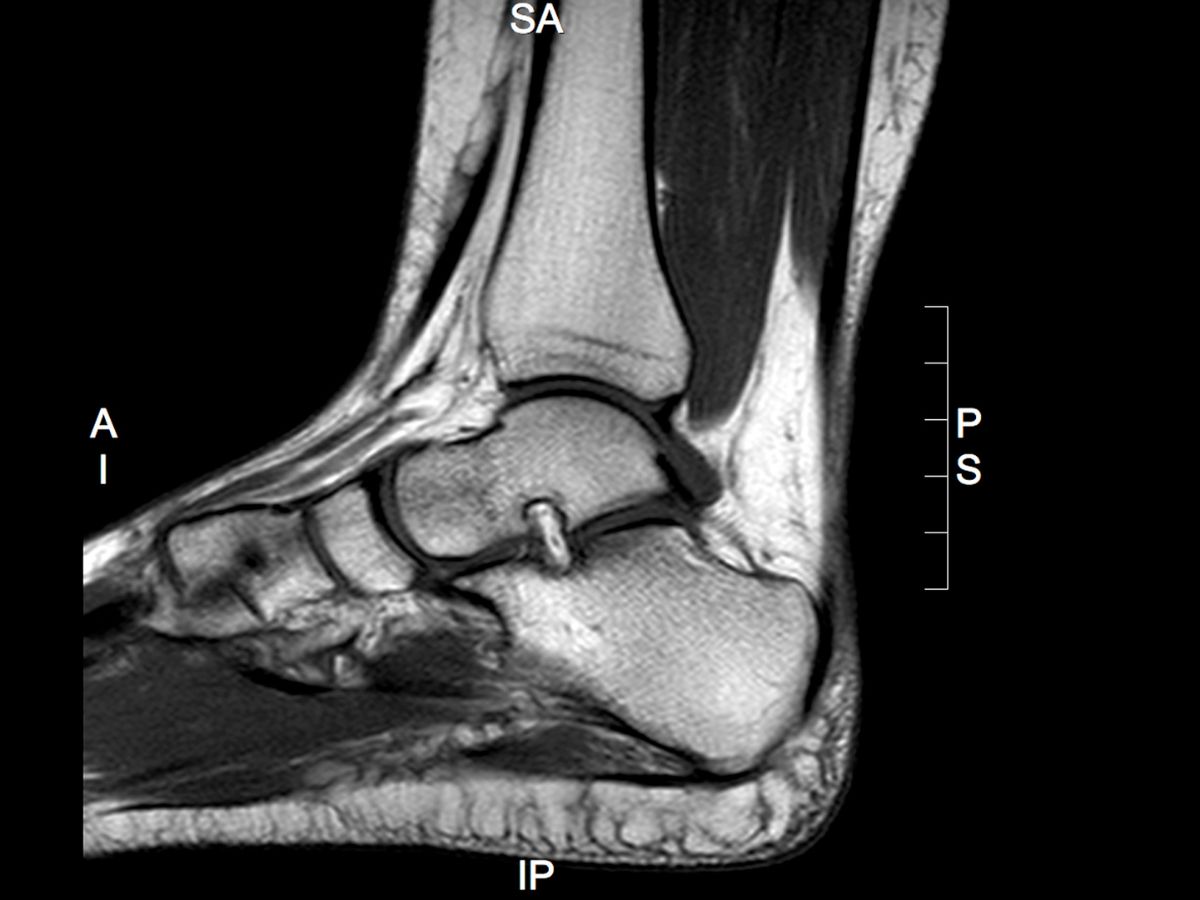

When to Refer for MRI in Foot and Ankle Conditions

Magnetic resonance imaging (MRI) plays an important role in the assessment of foot and ankle conditions, particularly where more detailed evaluation of soft tissue and